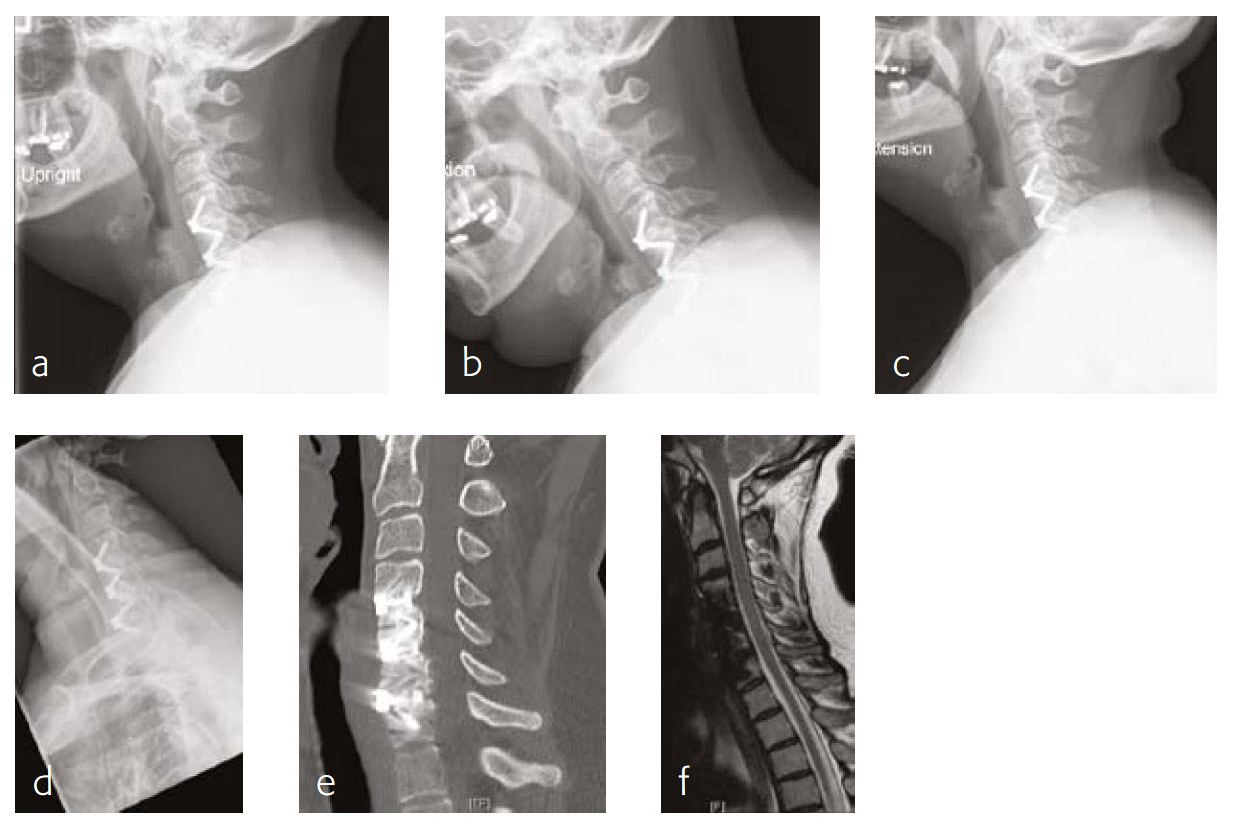

The patient works at a grocery store as a produce stocker and has a history of C5 through C7 ACDF done in 2005 (Fig 3). Her symptoms were relieved at that time, but she had quite severe neck pain and bilateral radicular symptoms. She had chronic C6 radiculopathy since recovery from that procedure, however, was able to return to work. Unfortunately, over the last 34 months, she has had a recurrence of symptoms, with constant neck pain and occasional cervicogenic headaches.

She will occasionally get bilateral pain, a pins and needles-type sensation through a number of distributions, including C5 through her shoulders, less occasionally through a C7 or C6 distribution. Movement of her neck was becoming increasingly painful, particularly with flexion and lateral flexion to the right and left.

She has tried a number of conservative modalities including narcotic pain medications, rest, heat, ice, physical therapy-type exercises, activity avoidance, and oral steroids. She states that she has had a steroid injection. These were not helpful for her. Eventually, she got an MRI and was found to have adjacent level disease.

On manual muscle testing, the patient had 5/5 strength bilaterally with shoulder abduction, elbow extension and flexion, wrist extension and flexion, finger abduction and grip strength.

The patient has appropriate range of motion through her cervical spine with flexion and extension, and lateral flexion and rotation. She gets grimacing pain with extreme ends of flexion as well as bilateral rotation and lateral flexion. She has no tenderness to palpation of the spinous process or paraspinous musculature of her cervical spine. She has decreased sensation in bilateral C5 distributions.

Follow-up (6 months)

The patient is now about 6 months status post a C4-C5 discectomy and interbody fusion with removal of preexisting C5 screws (Fig 4). She was recovering well and has not been taking any narcotic pain medication. She takes acetaminophen.

Case 3: A 46-year-old woman with neck pain and upper extremity paresthesia

A 46-year-old woman presented with one-year history of neck pain, upper extremity paresthesia, weakness, and subjective numbness (Fig 5). Her right upper extremity was worse than her left, with loss of function and debilitating pain. She described cramping in her upper extremities without etiology and without alleviating factors.

She had not been responsive to anti-inflammatory medications nor other nonoperative treatment including physical therapy. She had trouble with many of her activities of daily living due to breaks that must be taken due to her pain, as well as the inability to do certain things like open jars due to weakness.

Musculoskeletally, she had no obvious deformity in any of her extremities. Her bilateral upper extremities had strength testing of 5/5 in shoulder abduction, elbow flexion/extension, wrist extension/flexion, and finger abduction/flexion. Bilateral lower extremities showed 5/5 strength with hip flexion bilaterally, as well as bilateral 5/5 strength knee extension, dorsiflexion, plantar flexion of the ankle, and firing EHL.

She had sensation that is intact in all dermatomes. She had no pathological reflexes and no clonus. There was normal tandem gait.

Review of the patients outside imaging showed congenital stenosis of the cervical spine, as well as multilevel disk disease and concomitant acquired stenosis in the foramen of C4-C5, C5-C6, and C6-C7 where it was at its most significant level.

Follow-up (4 months)

At the 4-month follow-up, the patients symptoms were largely resolved and she has been able to return to work (Fig 6). She was very satisfied with her outcome. made significant progress in terms of his left upper extremity range-of-motion and strength.